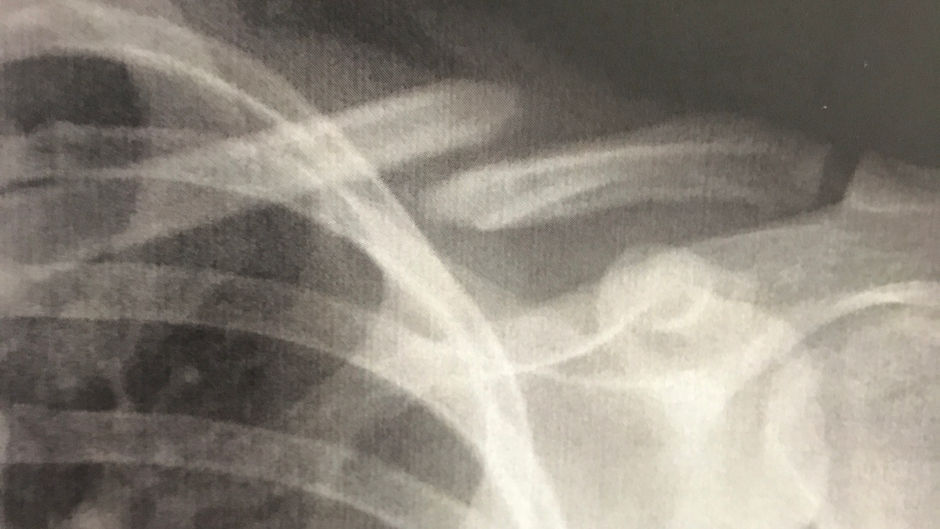

-ORTOPEDIA E TRAUMATOLOGIA

-CIRURGIA DO OMBRO E COTOVELO

-TRAUMATOLOGIA DO ESPORTE